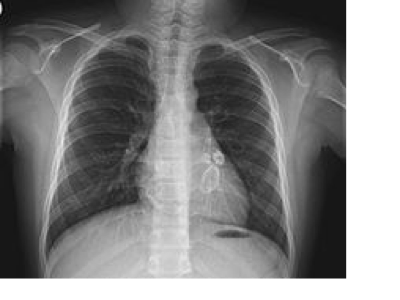

Diagnosis

No specific diagnostic tests, based off clinical signs and symptoms.